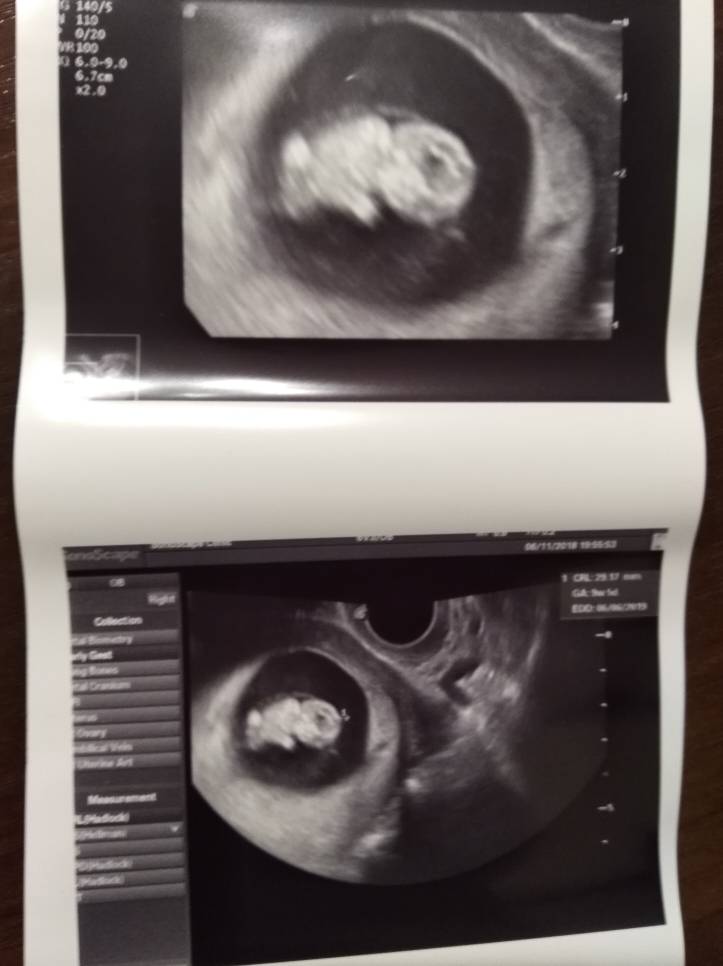

Wczoraj byłam u gina.

U dzidziulka wszystko w porządku.

Karta ciąży założona. Kolejna wizyta 22.11 (badania prenatalne).

A tutaj nasz wielkolud [emoji7]

Zobacz załącznik 914364

Jaki fajny człowiek!Termin mam na 10 czerwca. Wczoraj miałam usg już 2.5 cm